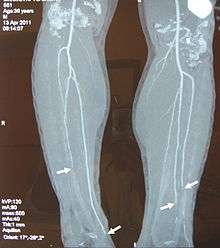

Complete occlusion of the right and stenosis of the left femoral artery as seen in a case of thromboangiitis obliterans | |

Angiograms of the upper and lower extremities can be helpful in making the diagnosis of Buerger’s disease. In the proper clinical setting, certain angiographic findings are diagnostic of Buerger’s. These findings include a “corkscrew” appearance of arteries that result from vascular damage, particularly the arteries in the region of the wrists and ankles. Collateral circulation gives "tree root" or "spider leg" appearance.[1] Angiograms may also show occlusions (blockages) or stenosis (narrowings) in multiple areas of both the arms and legs. Distal plethysmography also yields useful information about circulatory status in digits. To rule out other forms of vasculitis (by excluding involvement of vascular regions atypical for Buerger’s), it is sometimes necessary to perform angiograms of other body regions (e.g., a mesenteric angiogram).